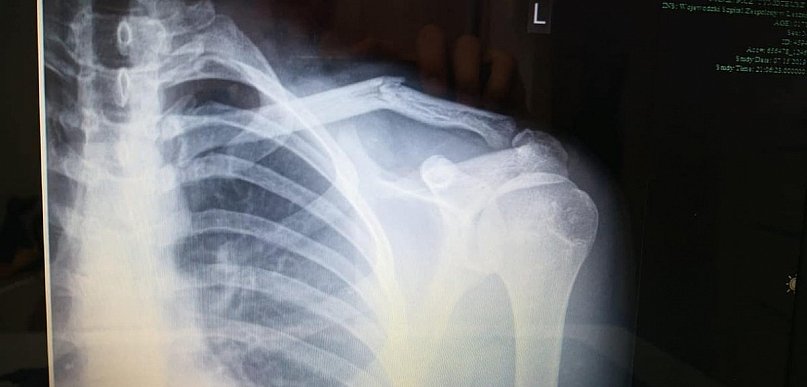

Tymoteusz Picz, żużlowiec Fogo Unii Leszno i Stainer Unii Kolejarza Rawicz, złamał obojczyk. Chłopak niedawno wyleczył kontuzję nogi. (...)